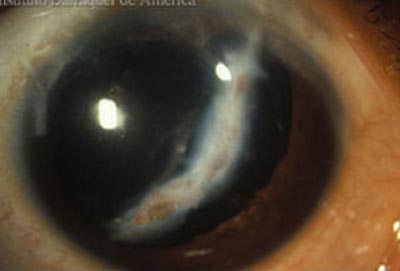

Queratocono

Queratocono

Queratografía

Es una enfermedad ectásica no inflamatoria que afecta la curvatura y el espesor de la córnea provocando su protrusión e irregularidad; es relativamente frecuente con una prevalencia del 54.5 por 100.000 (0.05%). Se da en todos los grupos étnicos, es bilateral y no existe predominio sexual. Su ocurrencia es mayor en personas que habitan tierras altas.

Su etiología todavía no está resuelta; entre 6 y 15% de los pacientes con queratocono, tienen familiares afectados. Se asocia a una larga lista de enfermedades sistémicas, pero su forma de presentación es esporádica y aislada. Su asociación mas frecuente es con la compresión, frote y restregado ocular, como trauma mecánico crónico.

Aparece en la pubertad, y por lo general el ritmo de progresión es mayor cuanto más joven es el paciente afectado. A medida que el queratocono progresa, la agudeza visual se ve comprometida por la distorsión que el cono genera, llegando a inhabilitar a la persona afectada para el desarrollo de una vida normal.